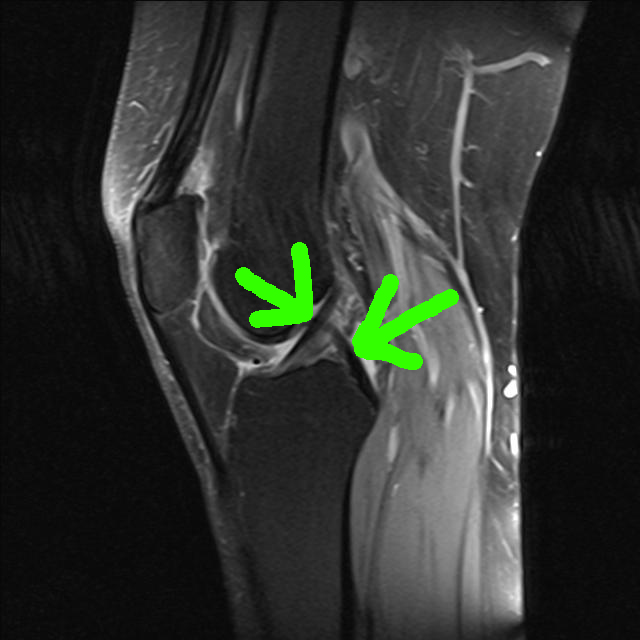

Der Innenmeniskus zeigt auf mehreren Bildern eine Auffälligkeit (Riss, rot markiert). Damals vor der Meniskus-OP am rechten Knie sah das MRT ähnlich aus, rechts ist der Außenmeniskus zu sehen (grüner Pfeil).

Die Kreuzbänder grüne Pfeile sind okay und ein bisschen Athrose (rote Pfeile) ist wohl auch dabei.